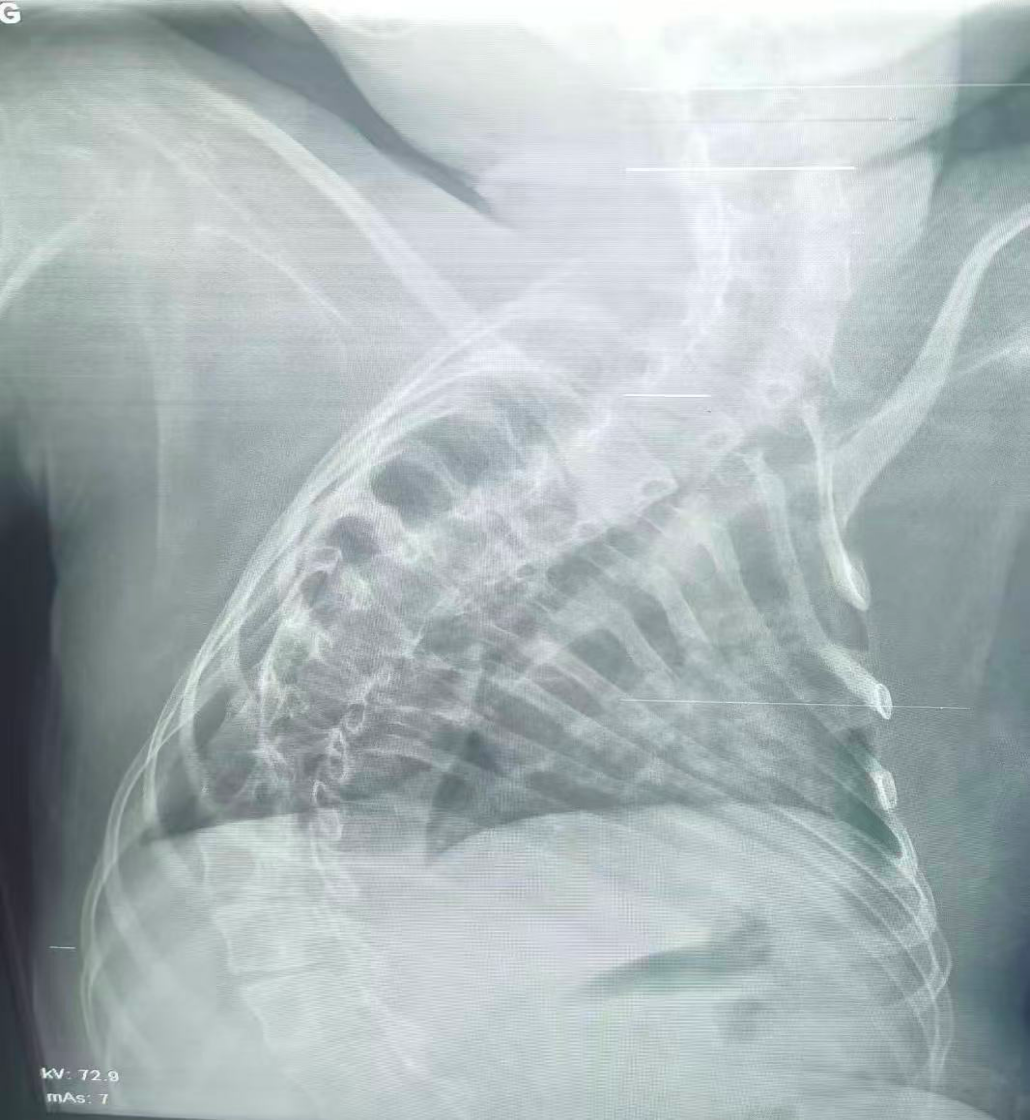

治療后

經(jīng)過團(tuán)隊(duì)的不懈努力,手術(shù)最終順利完成。術(shù)后患兒生命體征趨于平穩(wěn),氣道堵塞情況得到顯著改善,目前正在進(jìn)一步康復(fù)中。